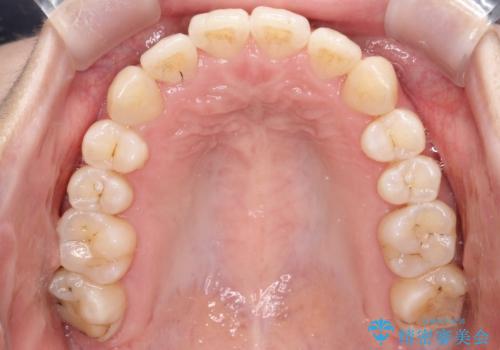

【インビザライン】前歯の凸凹をなおしたい

- 前歯の凸凹をなおしたいことを主訴にインビザラインにて矯正治療を行いました。

患者様にしっかりとインビザラインを使用して頂けたことで綺麗な仕上がりとなりました。